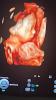

покидайте пожалуйста фотки 4d со 2скрининга 🫶🏼интересно посмотреть🥹

или 3d

так ручками закрыл личико 🥹